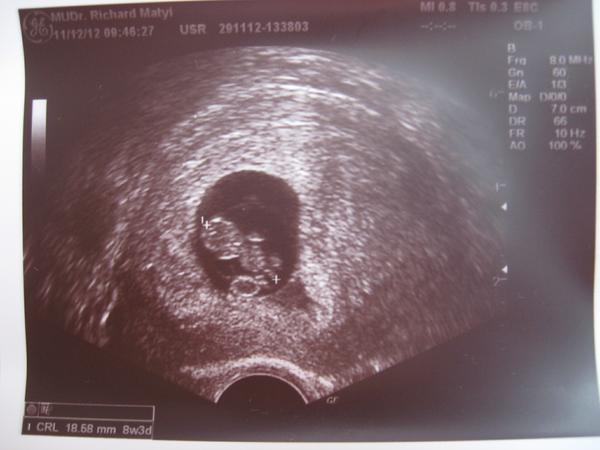

ahojte dievcata🙂) nasej laske druhemu pokladiku krasne bije srdiecko🙂)) a take je krasne🙂) myslela som si,ze si fotecku z usg brat nebudem,ale ked som tu babiku takmer 19 mm velku videla,tak som neodolala... 🙂)) podla usg to mam 8tt+3dni 🙂)) normalne som dnes roztopena od emocii🙂) keby mi pani vedla v cakarni nepovedala,ze si mam vyzut navleky z topanok,tak idem v nich az domov🙂)))) tu je fotecka🙂))a kazdej z vas tak velmi zo srdca prajem,aby ste taketo pokladiky mali co najskor v brusku a aby sa vam zdrave narodili🙂)))